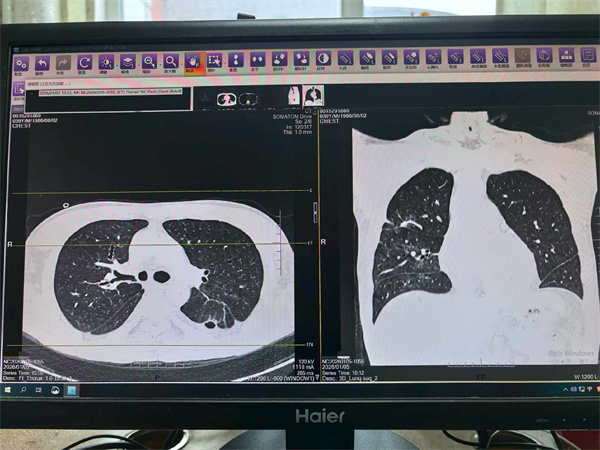

在后续CT检查中,医生发现其左肺形成了肺脓肿,并且发生了支气管胸膜瘘。“这意味着感染灶持续存在,像一个定时炸弹。”周利平教授说。为了彻底清除病灶,经过多学科团队的慎重评估,最终为他实施了左下肺叶切除术。当感染的核心被切除,这场持久战终于迎来了转折点。术后约一周,患者即出院返渝。据随访,患者复查肺部CT显示恢复良好。